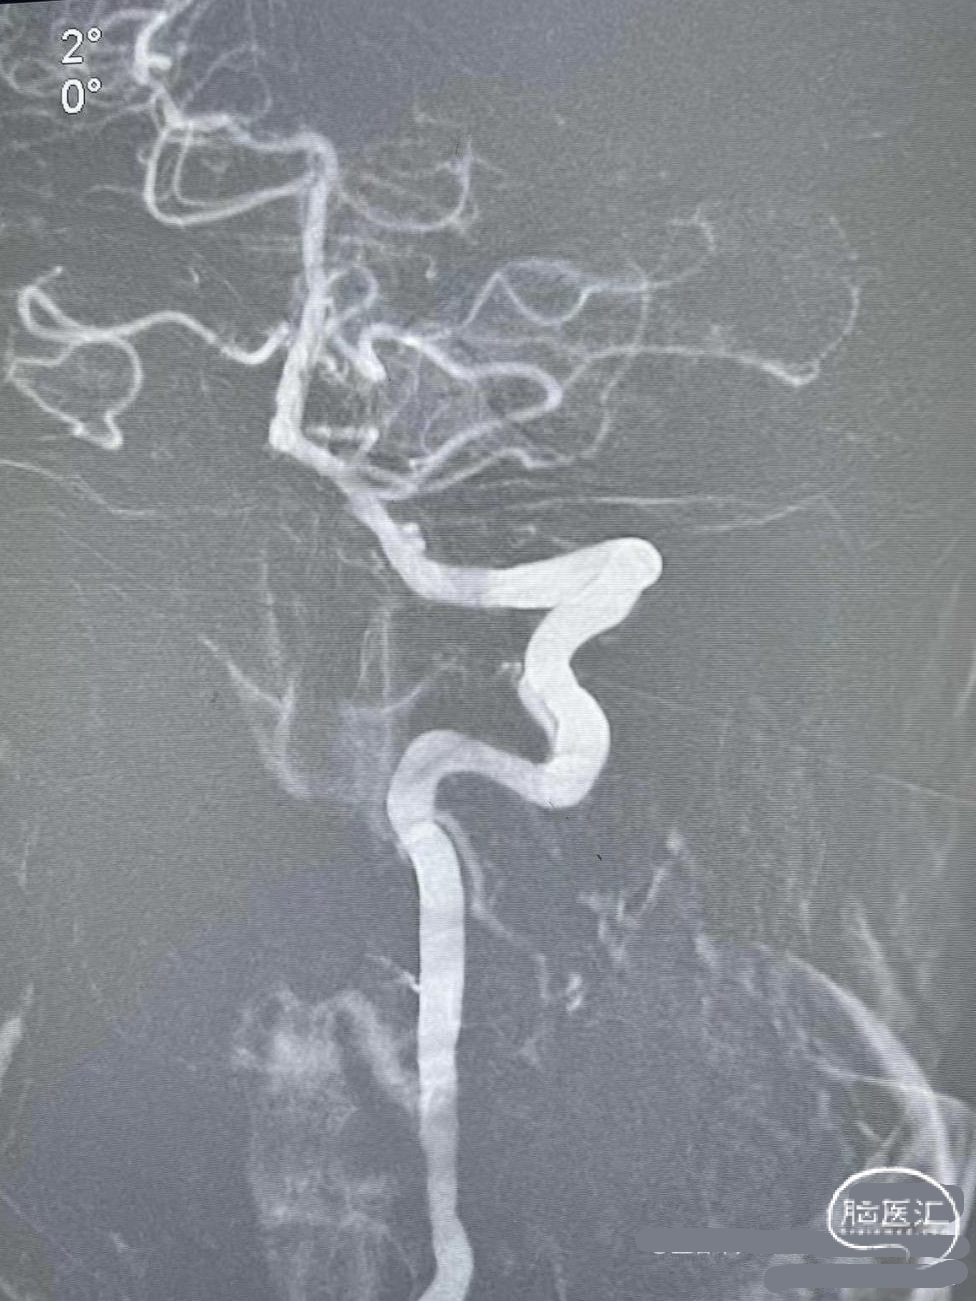

术后造影:

血管再通,前向血流3级。左侧为胚胎型大脑后。

术后CTA:Bridge药物支架形态良好,前向血流良好。

术后半年CTA:Bridge支架形态及贴壁良好,前向血流正常。